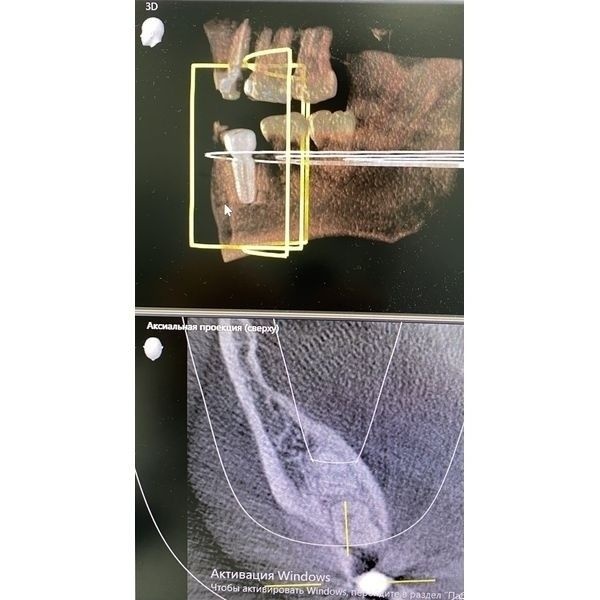

Компьютерная томографии выявила очаг разрушения костной ткани вокруг корня зуба с нечёткими контурами размером 1 × 2 мм. Нижнечелюстной канал находился в безопасном положении. В ходе диагностики также оценили целостность структур, плотность и размер альвеолярного отростка.